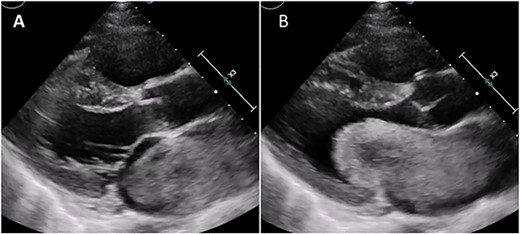

His vital sign was stable. Chest auscultation revealed an increased apical first heart sound. His chest X-ray detected cardiac enlargement (cardiothoracic ratio, 57%) and increased pulmonary markings. An electrocardiogram showed sinus tachycardia and a negative T wave in leads V1–V4. There were no episodes suspected paroxysmal atrial fibrillation. A transthoracic echocardiogram revealed a giant mass of 81 × 31 mm attached to the interatrial septum in the left atrium (Fig. 1A). The mass was floating and prolapsed into the left ventricle through the mitral valve orifice during diastole (Fig. 1B). Effective mitral orifice and mean pressure gradient via the mitral valve were |$\sim$|0.73 cm2 and 9 mmHg, respectively, and the mass affected for hemodynamics was equivalent to severe mitral stenosis. Mitral annulus was dilatated to 30 × 35 mm, and mild mitral valve regurgitation was observed. Enlargement of left atrium was 43 mm in the anteroposterior diameter. Right atrial and ventricular dilatation, moderate functional tricuspid valve regurgitation and severe pulmonary hypertension with the right ventricular systolic pressure of |$\sim$|88 mmHg were also observed. Biochemical tests showed that a high brain natriuretic peptide value of 661 ng/ml and tumor markers of carcinoembryonic antigen(CEA), CA19–9, interleukin-2 receptor were within the normal limits. He was diagnosed with congestive heart failure of NYHA III due to a giant mass. No clinical findings of cerebral infraction were observed. He was then transported to our hospital. Urgent surgical mass resection and tricuspid annuloplasty were planned.

Transthoracic echocardiogram during systole (A) and diastole (B). Giant LA myxoma was prolapsing to the mitral valve orifice.